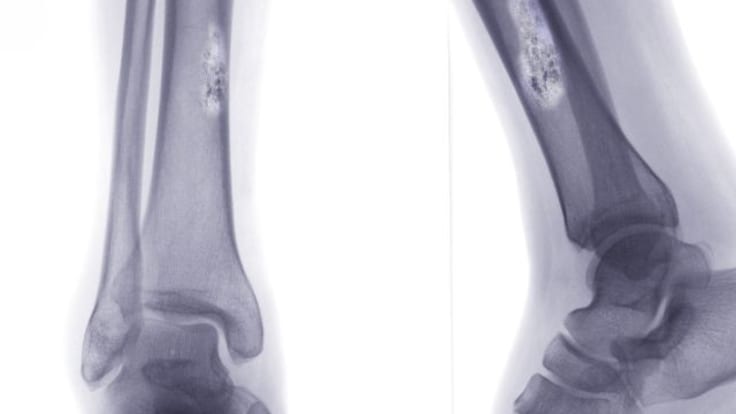

Radiographie

La radiographie permet de déceler des anomalies au niveau des os, une excroissance, voire un trou. Il est difficile néanmoins de conclure avec cet examen si la tumeur décelée est cancéreuse ou non. Dans certains cas, il permet néanmoins d'écarter le diagnostic de cancer comme dans la maladie de Paget.

L' ostéosarcome touche généralement les os du tibia et du fémur (os longs), mais aussi le genou. Cette tumeur rare et agressive touche souvent les jeunes hommes.

Tibia, jambes, genoux

Le cancer des os touche souvent le tibia, le fémur, les genoux, le bassin, les jambes, ou les cartilages. Ces zone sont concernées par les trois formes de cancer des os les plus fréquentes : ostéosarcome, sarcome d'Ewing et chondrosarcome.